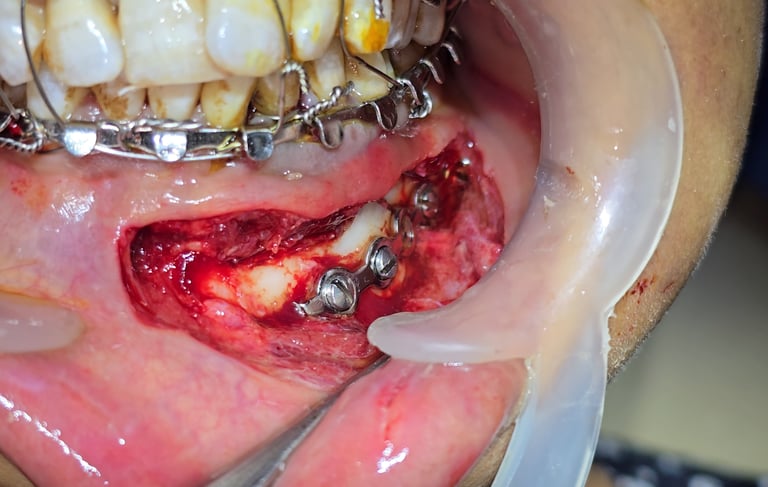

Definitive Surgical Management with Open Reduction and Internal Fixation (ORIF)

Reduction of fractured segments under general anesthesia.

Plating with mini-plates and screws in parasymphysis and angle regions.

Condylar and coronoid fractures aligned with supportive stabilization.

Wound closure was done with proper suturing technique.